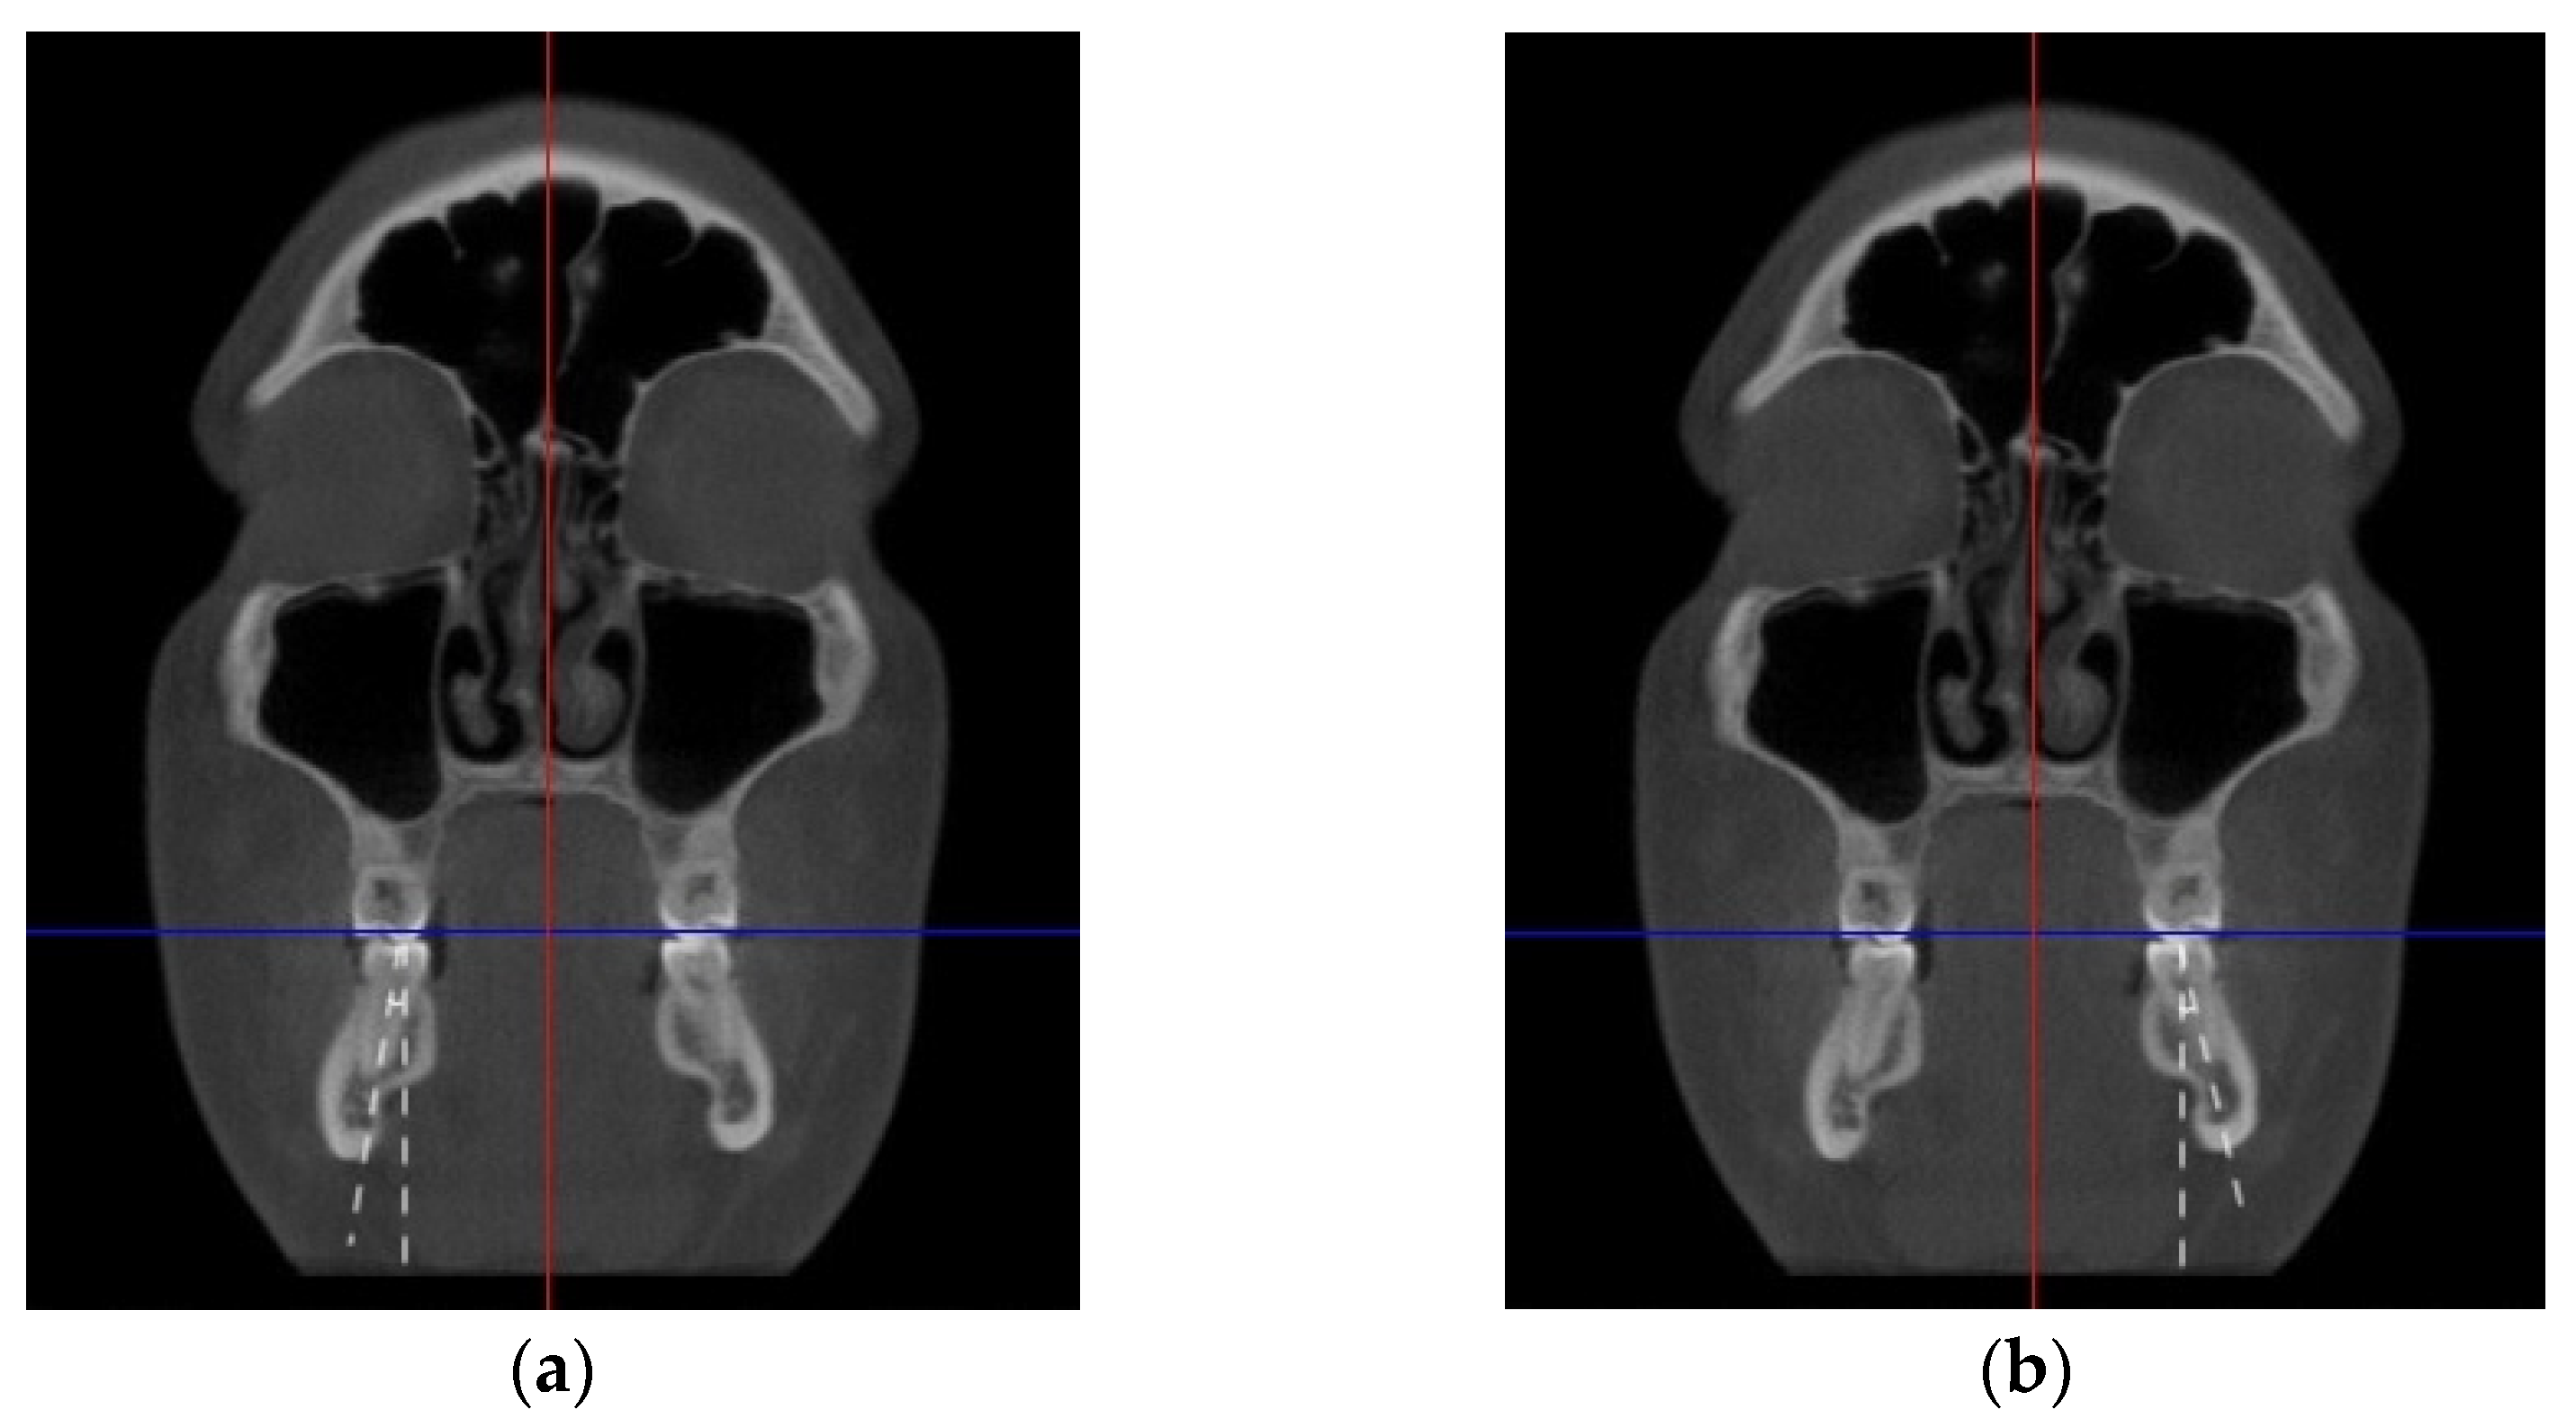

2. Materials and Methods